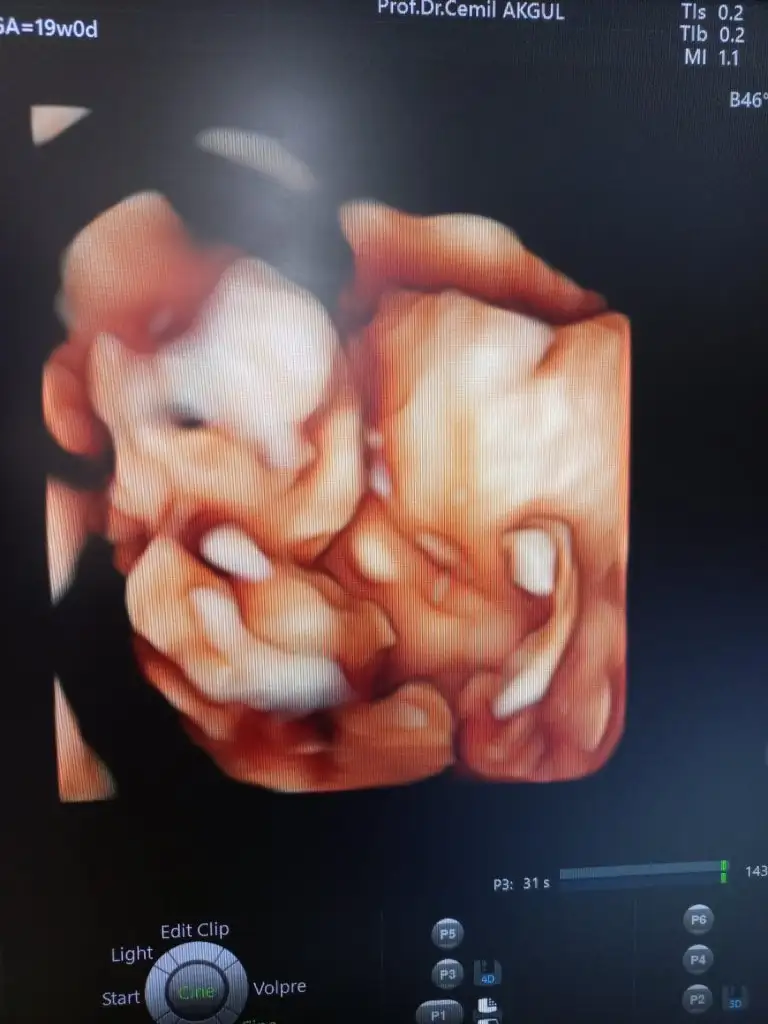

Kizlar dun pek giremedim dunki kontrolu detaylı anlatim biraz dun 19 haftaliktik haftasiyla uyumlu bebisim ama ben 1.5 kilo almisim daha doktor artik kilo alman lazim ileride allah korusun bebekte gelisim gerili olur seninde kilo alman lazim dedi benim doktorun ultrason detayli oldugu icin ger ay detayliya girmis oluyorum herseyine bakti hersey yolunda dedi kasik agrimi soledim yine onemsemedi daha ilerleyen zamanlarda sirt bel agrilari carpintilar vs olucak hamilelikte bunlar normal dedi. Tetenoz aşisini sordum ol dedi ve seker yuklemesi icin recete tazdi 23.haftada onu yaptiricam 5 hafta sonra ya cagirdi taa bitek ona uyuz oldum zaman gecmiyor cunku hic suan artik yavaslayan döneme girdik ilerleyen haftalarda daha sık cagiricam dedi haziran ortalarinda hersey yolunda giderse dogum gorunuyor ve benim zilli kizim okadar hareket etsin diye bekledim doktora gitmemi beklemis aksaminda baya icimde kipirti hissettim doktorada sormuştun yavas yavas kelebek cirpmalari baslar bi kac haftaya net hissedersin dedi ☺️birde dedimki ben balik hic yiyemiyorum onemli degil yumurta yogurt ayran ceviz peynir bunlardanda alirsin dedi birde dedim benim gobegim neden buyumuyor kilo almadigin icin dedi😅 oyle simdi ta 5 hafta beklicem subat bos gecicek 4 martta randevum buda kizimin net olmayan goruntusu🫠🫠🫠

Eklentiler

• 011bcfdc-def8-4168-ba81-1eae33cfd8ec.webp

011bcfdc-def8-4168-ba81-1eae33cfd8ec.webp

31,5 KB · Görüntüleme: 54